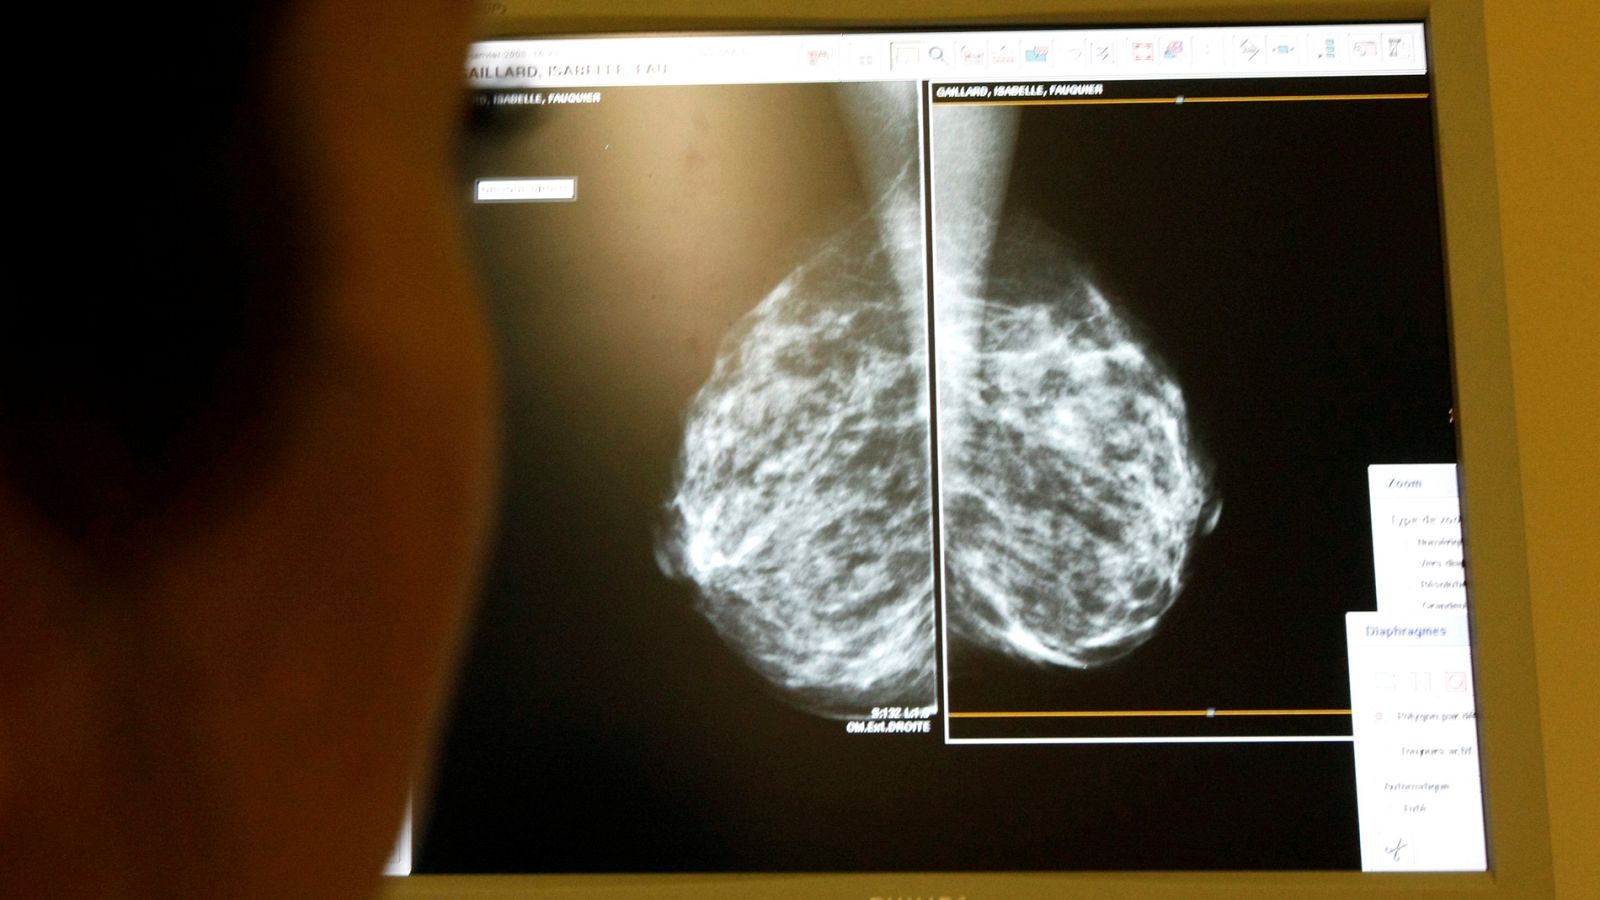

Radiografía de una mamografía

RTVE.es/AGENCIAS